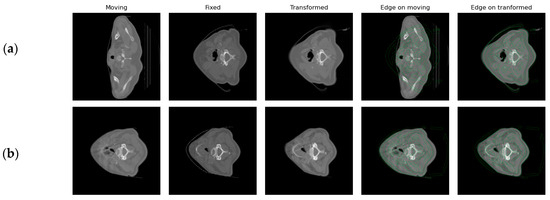

3.5. Results on the Registration Expansion Framework

Following the segmentation framework, the registration feasibility study was implemented. In Figure 5, an example output from the registration process is presented. Moving refers to the image to be aligned with the fixed image. Transformed image refers to the results of the registration process. In the final two images of each row, the edges of the fixed image (reference) are presented on top of the moving and moved images in order to qualitatively assess the performance of the utilized registration method according to the edges of the image. The first row shows an example of the first registration step, where the pCT image is registered to the CBCT1 (week 1), while the second row shows an example of the second registration step, where the CBCT1 is registered to the CBCT5 (week 5). In Figure 5a, the pCT and CBCT images present a larger difference and the number of slices is not the same. Due to this fact, moving and fixed images are far apart and the edges of the fixed image do not match the edges of the moving image. However, registration manages to bring them to approximately the same space, which can be seen both in the similarity between the fixed and the transformed image and in the alignment of the edges of the fixed image when they are superimposed on the transformed image. In Figure 5b, an example pair of the registration between CBCT1 and CBCT5 shows the smaller difference between them before registration, as well as the ability of the second registration step to align images and their edges.

As presented in Figure 5a,b, the transformed image is more similar to the fixed one, whereas the edges of the fixed image are closer to the real edges in the transformed image. On the moving image, it can be observed that the edges of the fixed image initially do not match the real edges of the moving one, while after registration, the edges of the fixed image are aligned with the transformed image.

Figure 5. An example of the registration processes for (a) pCT to CBCT1; (b) CBCT1 to CBCT5.